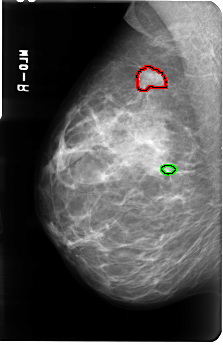

FILE: B_3040_1.RIGHT_MLO.OVERLAY

TOTAL_ABNORMALITIES 2

ABNORMALITY 1

LESION_TYPE MASS SHAPE IRREGULAR MARGINS SPICULATED

ASSESSMENT 4

SUBTLETY 4

PATHOLOGY MALIGNANT

TOTAL_OUTLINES 1

BOUNDARY

ABNORMALITY 2

LESION_TYPE MASS SHAPE OVAL MARGINS CIRCUMSCRIBED

ASSESSMENT 3

SUBTLETY 3

PATHOLOGY UNPROVEN